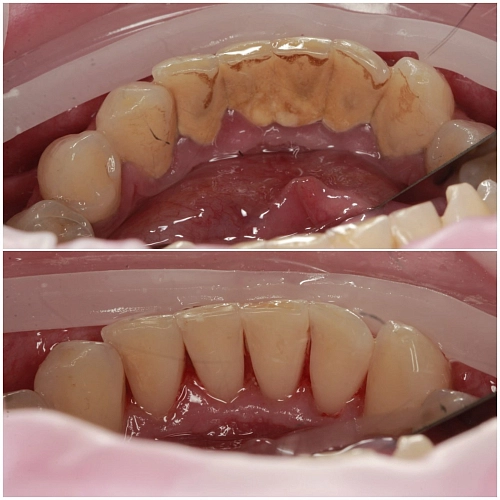

Почему любое лечение начинается с профгигиены?

В слюне и ротовой жидкости в среднем содержится больше 100 микроорганизмов в 1 миллилитре, а в зубном налёте — больше 1000 в 1 грамме. Во рту может одномоментно обитать 688 видов различных бактерий. Чтобы бактерии не попали в рабочую зону, ее при лечении изолируют стерильными салфетками и дезинфицируют, потому что в противном случае велик риск вторичного кариеса под пломбой. В процессе профгигиены мы удаляем  микробную пленку, которая образуется уже в течение двух часов после чистки зубов пастой. Если ее не убрать, то все эти микробы попадают под пломбу.

Также профгигиена необходима перед реставрацией. Доктору важно попасть в цвет,  так как налёт на зубах скрывает естественный оттенок.